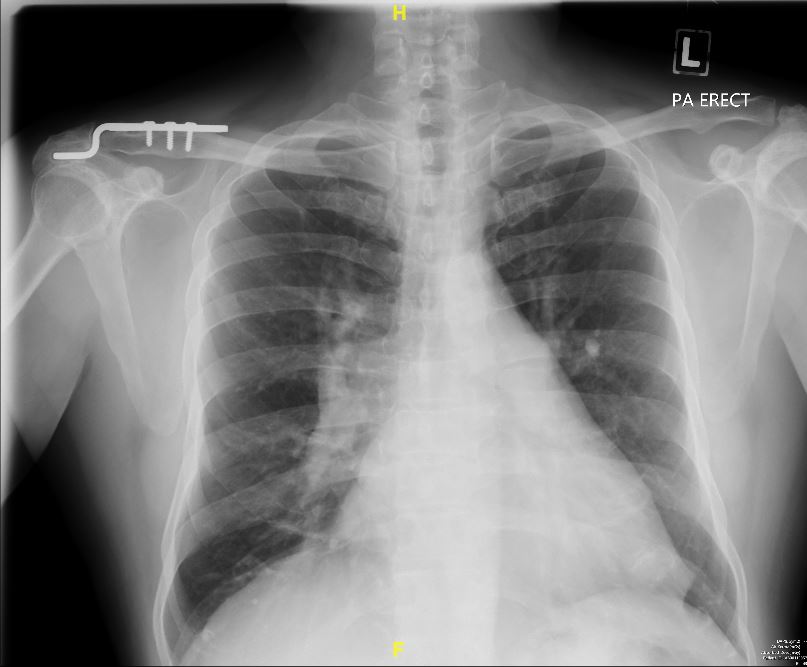

A 57-year-old asymptomatic man underwent a routine chest X-ray revealing perihilar haziness, indicative of pulmonary artery enlargement. A cardiology evaluation revealed a split second heart sound with a loud P2 & a right-sided, pansystolic murmur over the tricuspid area suggest a possible atrial septal defect (ASD) with tricuspid regurgitation. Changes of right heart dilatation like right axis deviation, P-pulmonale & right ventricle hypertrophy are absence in electrocardiography.